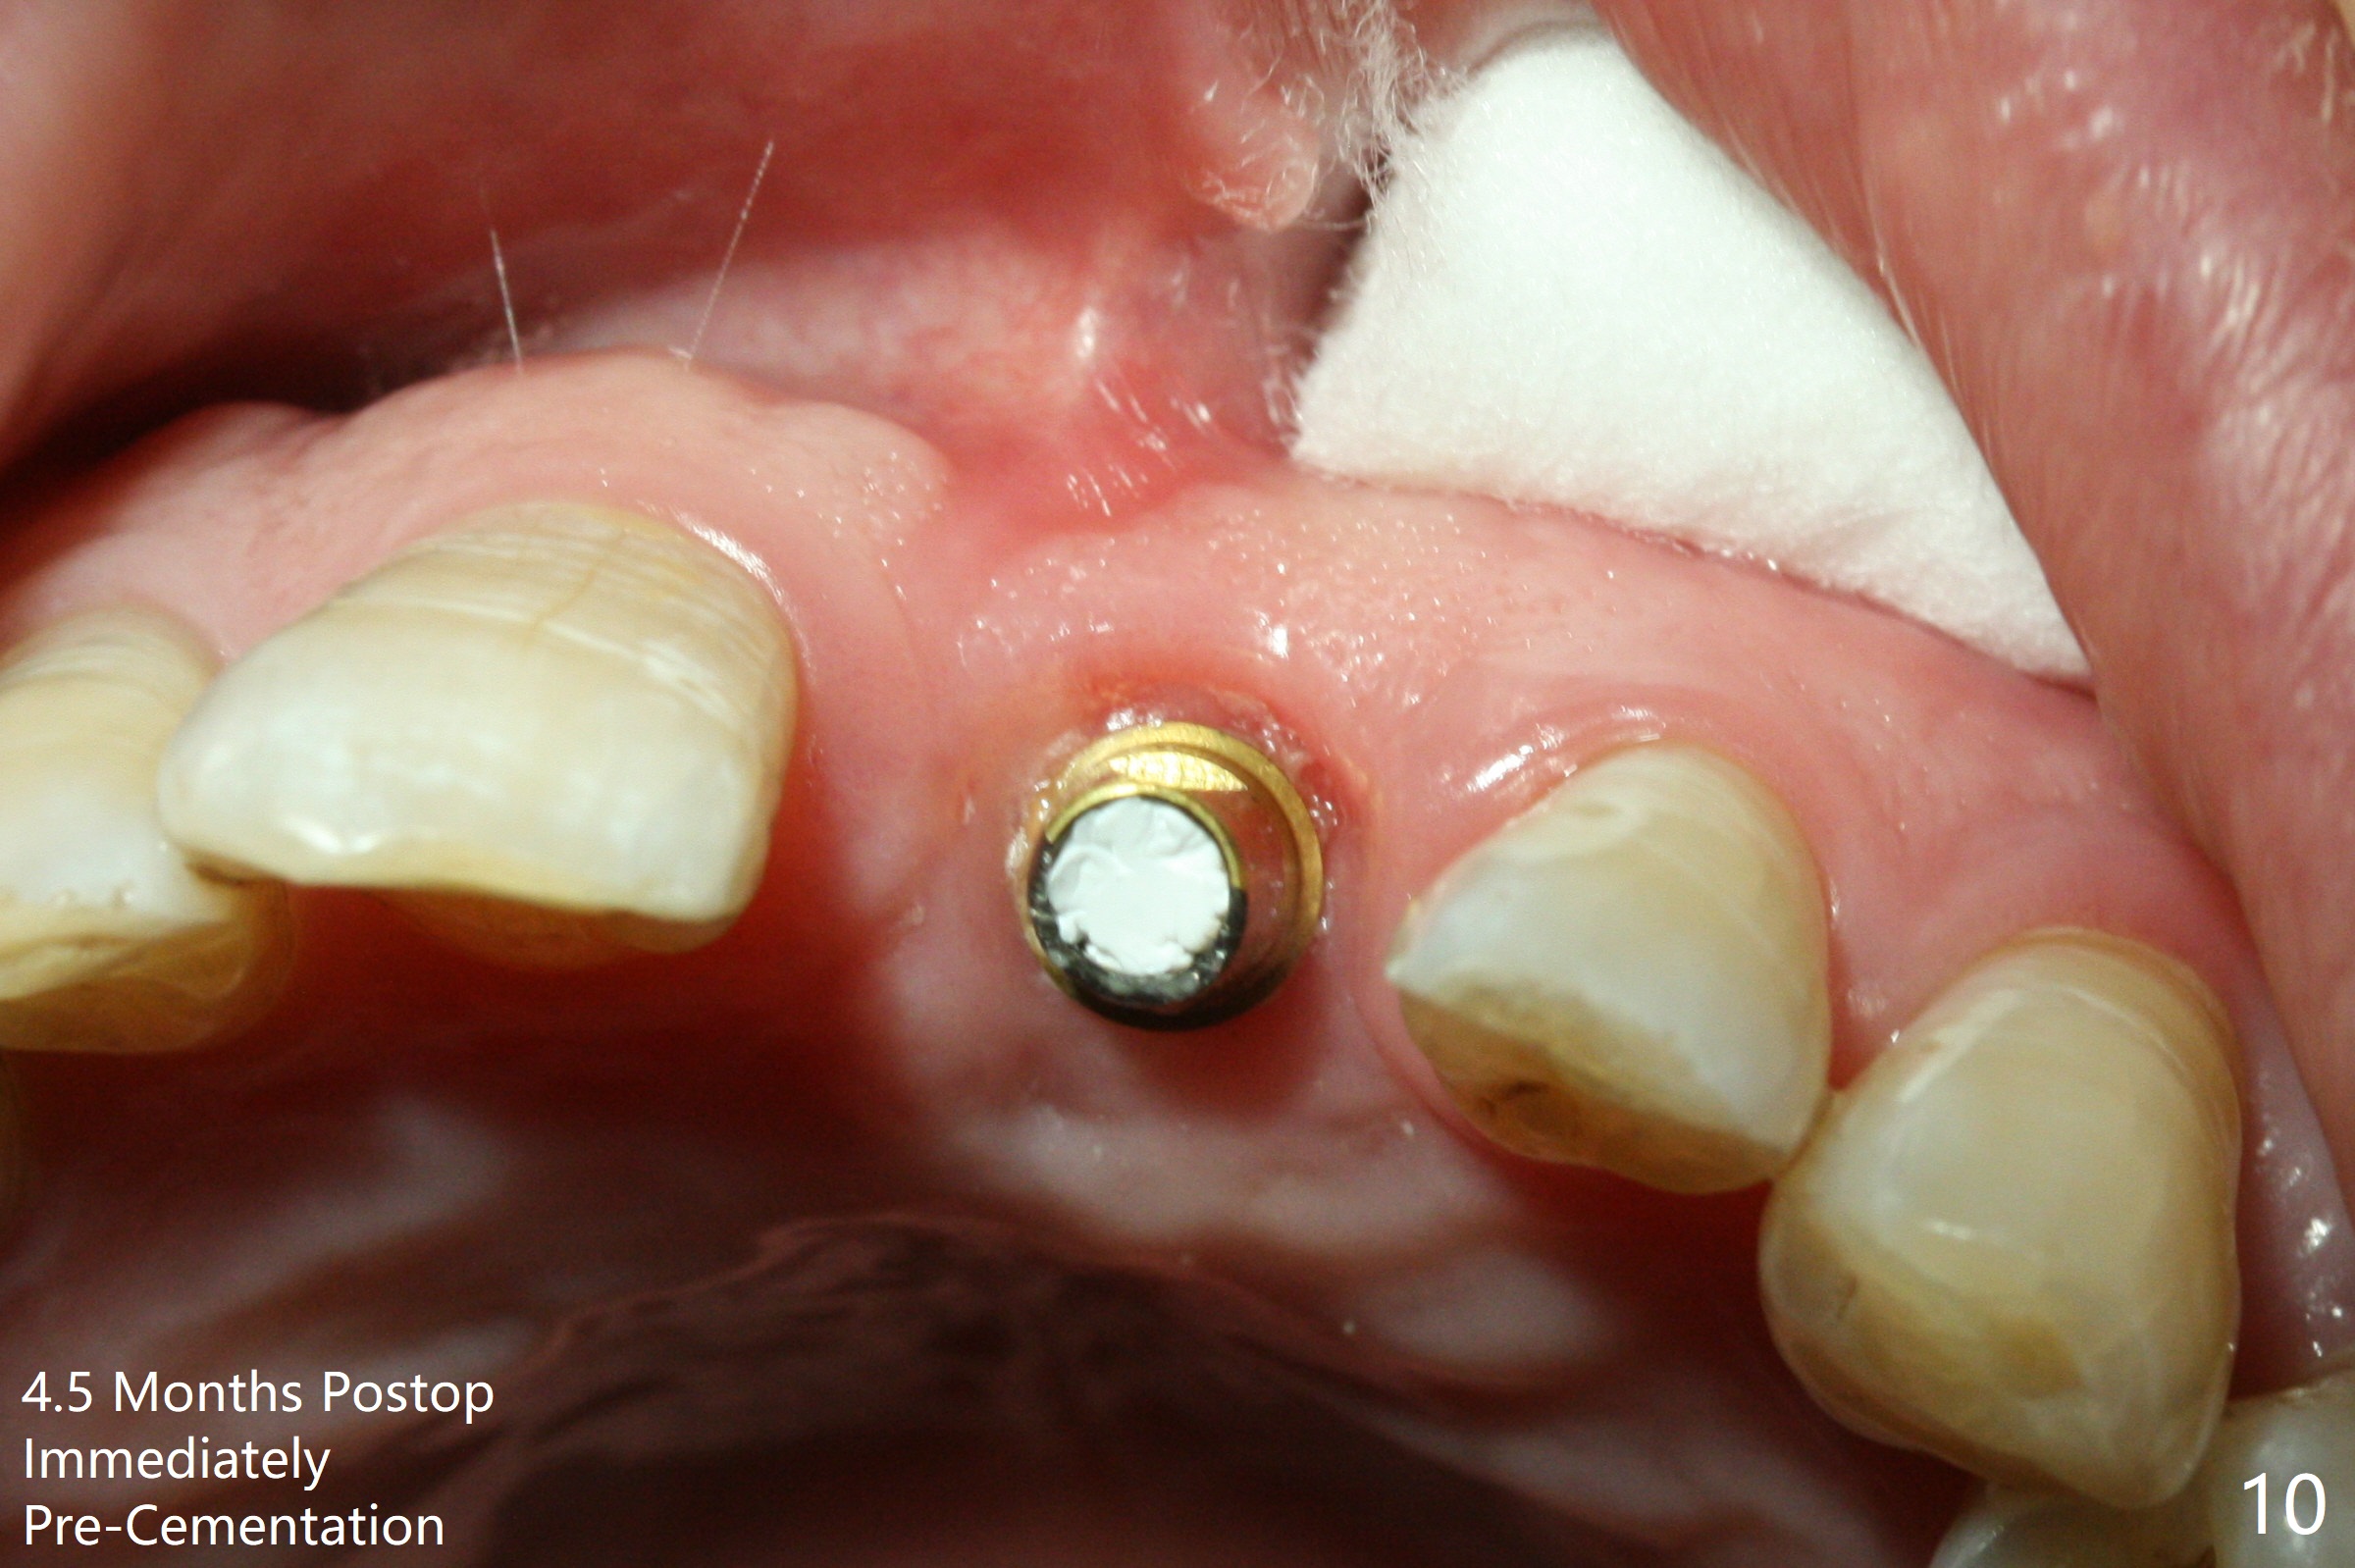

Preop examination shows mobility I of the teeth #8 and 10 and apparent occlusal trauma from #22-26 implant bridge. After occlusal equilibrium, incision reveals low, but moderate ridge at #9 (Fig.1). Fig.2a is a cross section of a normal upper incisor socket with thin buccal plate (B) and thick palatal one (P). It is difficult to initiate osteotomy in the oblique palatal wall when the buccal plate is resorbed (Fig.2b). In this case with horizontal buccal and palatal plate bone loss, the socket bottom is flat (Fig.2c), easy for osteotomy (Fig.2d green arrow, Fig.3). The initial osteotomy deviates mesial (Fig.3). To avoid perforation into the Incisive Canal, the trajectory is changed (Fig.4). After use of the final drill (3 mm), the coronal Incisive Canal is perforated. Following placement of a 3.5x13 mm implant and 4.5x5.5(4) mm abutment, Vanilla Graft is placed (Fig.5 *) to repair the perforation. Retrospectively, the coronal end of the Incisive Canal is revealed at incision (Fig.1 *). The initial osteotomy should be slightly more distal (Fig.3 black line). The buccal plate looks bulky due to placement of the abutment and bone graft 1 week postop (Fig.6,7 (crown dislodgement)). The bone graft appears to remain in place 2 months postop (Fig.8). Impression is taken because of instability of the immediate provisional (Fig.9 after Laser gingivectomy). The gingiva and buccal plate remain healthy 4.5 months postop (Fig.10). A permanent crown is cemented (Fig.11).